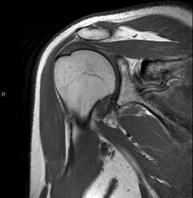

- RM d'Espatlla

Exploració per a l'estudi de lesions en els tendons, els músculs i les articulacions. La seva principal utilitat resideix en diagnosticar les lesions dels tendons del braçal rotatori. Té una durada aproximada de 20 minuts. No utilitza radiació ionitzant. - RM de Braç